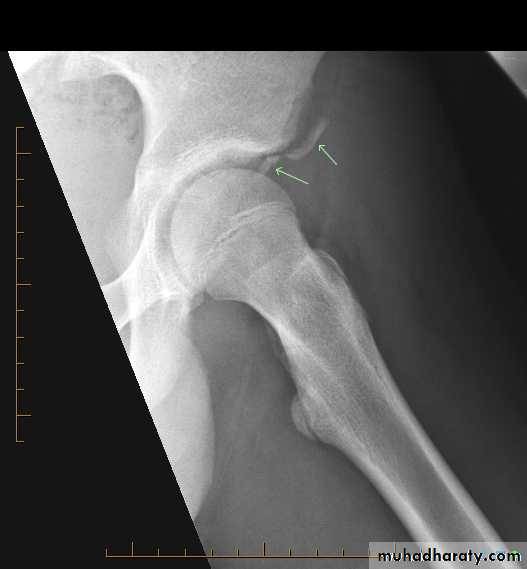

• Radiographs

• Anteroposterior pelvis

• CT

Classification

Young-Burgess based on injury mechanism.

1- Lateral compression (LC)

2- Anteroposterior compression (APC)—all have symphyseal diastasis.

3- Vertical shear (VS)

Usually due to a fall. Vertical displacement of hemipelvis commonly with complete disruption of the SI joint.4- Combined mechanism